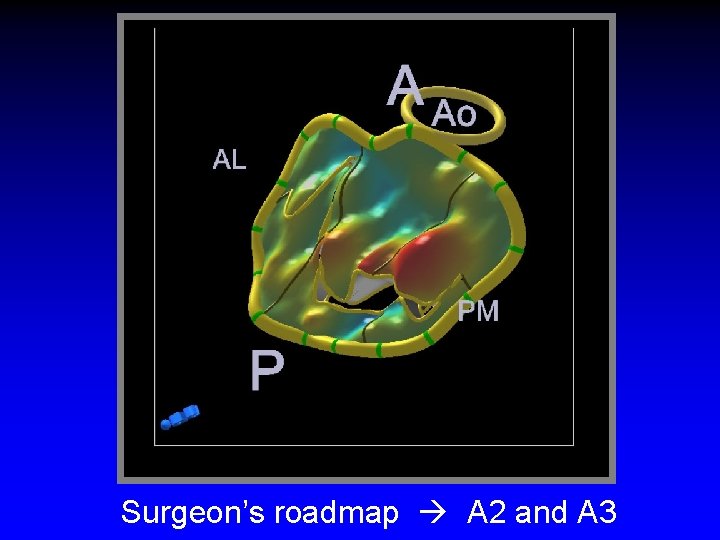

Roadmap for the surgeon

Case 3 Ruptured cords A 2 and A 3

Surgeon’s roadmap A 2 and A 3